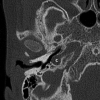

Results: There were 26 patients (52 ears) with a CT or MR imaging scan available. A dense stapes superstructure was found in 18 ears (36%), an incomplete partition type II was suspected in 12 cochleas (23%), the lateral semicircular canal was malformed with a small bony island in 17 ears (33%), and the lateral semicircular canal and vestibule were fused to a single cavity in 15 ears (29%).

Conclusions: Middle and inner ear abnormalities were frequently encountered in our cohort, including malformations of the lateral semicircular canal.